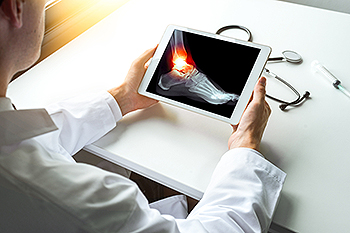

A broken toe is a fracture in one of the small bones of the toes, usually caused by direct impact or repeated stress. It often appears with symptoms consisting of sudden pain, swelling, bruising, and difficulty walking. Some people notice the toe looks misaligned or feels tender when touched. This injury can happen from stubbing the toe, dropping a heavy object, or from overuse in sports. Risk factors include weak bone density, wearing poor footwear, and active lifestyles that involve running or jumping. Healing time varies, but most cases improve over several weeks with proper care and protection. A podiatrist can confirm the fracture with imaging, ensure proper alignment, and guide treatment to avoid long term problems. If you have broken your toe, it is suggested that you consult a podiatrist who can guide you to an appropriate treatment plan.

Although most people try to avoid foot trauma such as banging, stubbing, or dropping heavy objects on their feet, the unfortunate fact is that it is a common occurrence. Given the fact that toes are positioned in front of the feet, they typically sustain the brunt of such trauma. When trauma occurs to a toe, the result can be a painful break (fracture).

Severe toe fractures may be treated with a splint, cast, and in some cases, minor surgery. Due to its position and the pressure it endures with daily activity, future complications can occur if the big toe is not properly treated.

To figure out the cause of foot pain, podiatrists utilize several different methods. This can range from simple visual inspections and sensation tests to X-rays and MRI scans. Prior medical history, family medical history, and any recent physical traumatic events will all be taken into consideration for a proper diagnosis.

The Achilles tendon is the strong band of tissue that connects the calf muscles to the heel bone, and helps the foot push off during walking and running. Injuries to this tendon may develop from overuse, sudden strain, tight calf muscles, or long-term degeneration. Many people notice pain, swelling, stiffness, or tenderness near the back of the heel, especially during activity or after rest. In some cases, the tendon may partially tear or weaken, over time. Imaging studies can help a podiatrist identify the exact problem and determine how severe the injury has become. Ultrasound and magnetic resonance imaging, also called MRI scans, allow detailed views of the tendon and surrounding tissue. These tests help guide treatment, which may include bracing, orthotics, targeted exercises, anti-inflammatory care, or surgery, for more advanced injuries. Early diagnosis can improve healing and help prevent rupture. If Achilles tendon pain continues to worsen or limit movement, it is suggested that you visit a podiatrist for an evaluation and appropriate treatment.

Achilles tendon injuries are diagnosed by a thorough physical evaluation, which can include an MRI. Treatment involves rest, physical therapy, and in some cases, surgery. However, various preventative measures can be taken to avoid these injuries, such as:

An isolated medial malleolar fracture is a break in the inner part of the ankle, at the bony bump on the inside called the medial malleolus. The word isolated means the fracture occurs on its own, without other parts of the ankle being broken. This injury often happens from a sudden twist, fall, or direct hit during sports or everyday movement. Common symptoms include pain, swelling, bruising, and trouble putting weight on the foot. Even though the break is in one area, it can still affect balance and walking. A podiatrist can diagnose the injury with an exam and imaging, then guide treatment such as casting, bracing, or surgery, if needed. This type of doctor also monitors healing to help restore movement safely. If you have ankle pain after an injury, it is suggested that you seek care from a podiatrist.